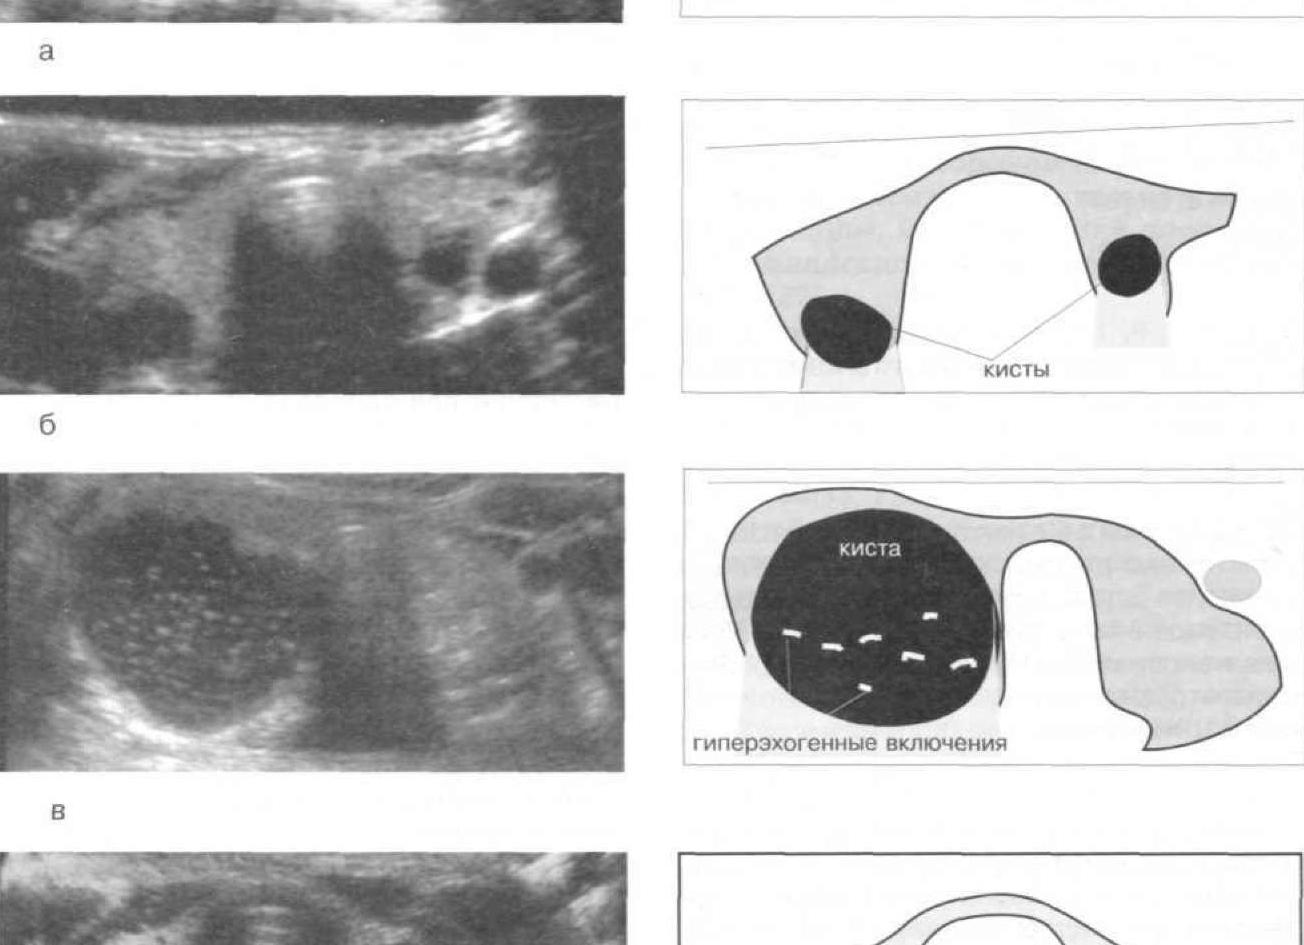

Иногда в УЗИ-заключениях в яичнике – левом или правом врач пишет о наличии анэхогенных образований. Эхогенность – это термин, применяемый в ультразвуковой диагностике для обозначения проводимости тканями ультразвуковых волн. Такие ткани, как кость, полностью отражают ультразвук из-за своей высокой плотности, также он полностью отражается на границе органов и тканей, которые содержат воздух. Плотные ткани сильнее отражают ультразвук, а те, в которых содержится много жидкости, проводят сигнал ультразвукового датчика, усиливая его при этом.